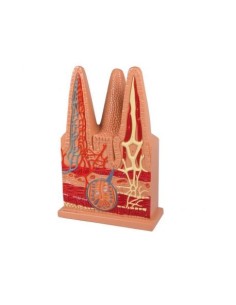

3B Modèle scientifique et anatomique : Pathologies de l'intestin K55